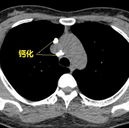

钙化在MRI上都是低信号吗?